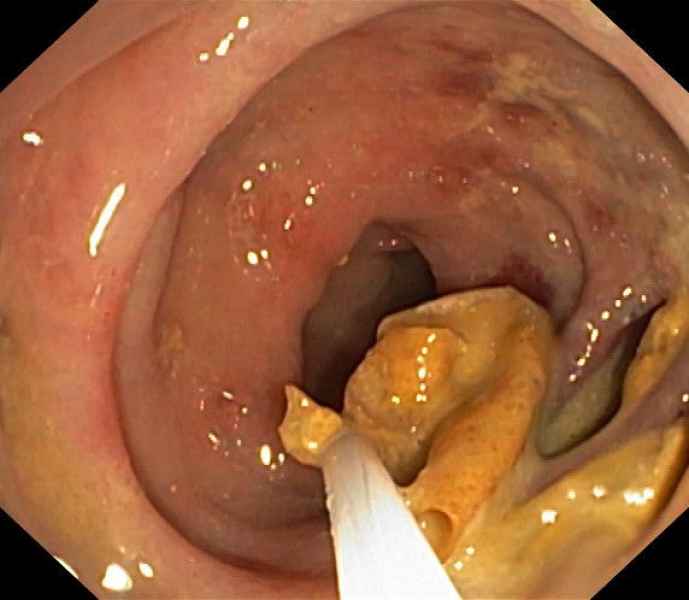

Diaphragm disease: Non-Steroidal Anti-Inflammatory Drug - Induced Enteropathy

Fotografia